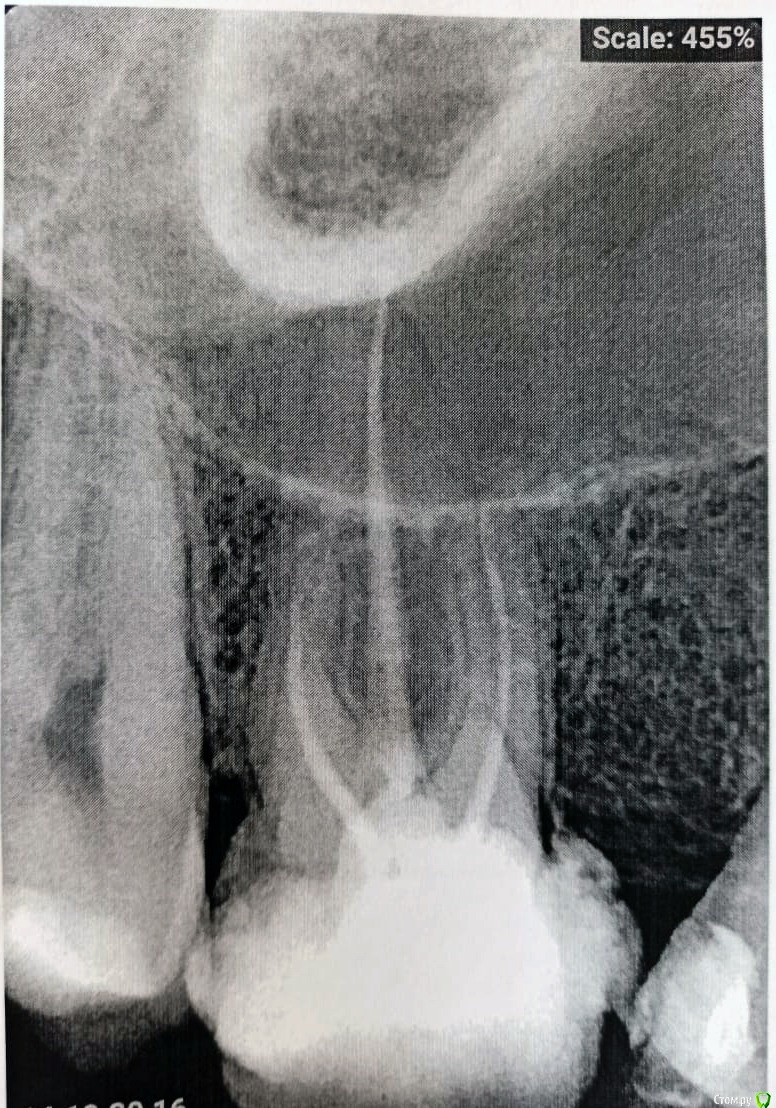

Лазарсон Опубликовано 3 ноября, 2020 Поделиться Опубликовано 3 ноября, 2020 Уважаемые врачи, если возможно что-то разглядеть на снимке такого качества, то подскажите, до конца ли запломбированны каналы? Ссылка на комментарий

Лазарсон Опубликовано 3 ноября, 2020 Автор Поделиться Опубликовано 3 ноября, 2020 Здравствуйте, а что Вас беспокоит?Физически этот зуб не беспокоит, там временная пломба сейчас. Просто показалось что не до конца запломбированный каналы. Врач говорит все норм, я просто для себя, перестраховаться )) Ссылка на комментарий